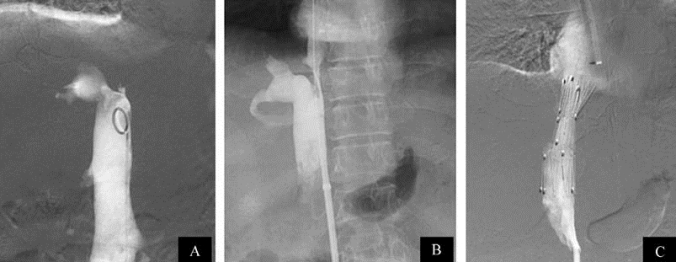

图21-20 Budd-Chiari综合征球囊血管成形术(二)

A.主肝静脉完全闭塞(长箭头处),副肝静脉异常扩张(短箭头处)伴有与下腔静脉之间膜性狭窄;B.通过下腔静脉行副肝静脉破膜后进行球囊扩张;C.治疗后造影示副肝静脉顺利引流入下腔静脉